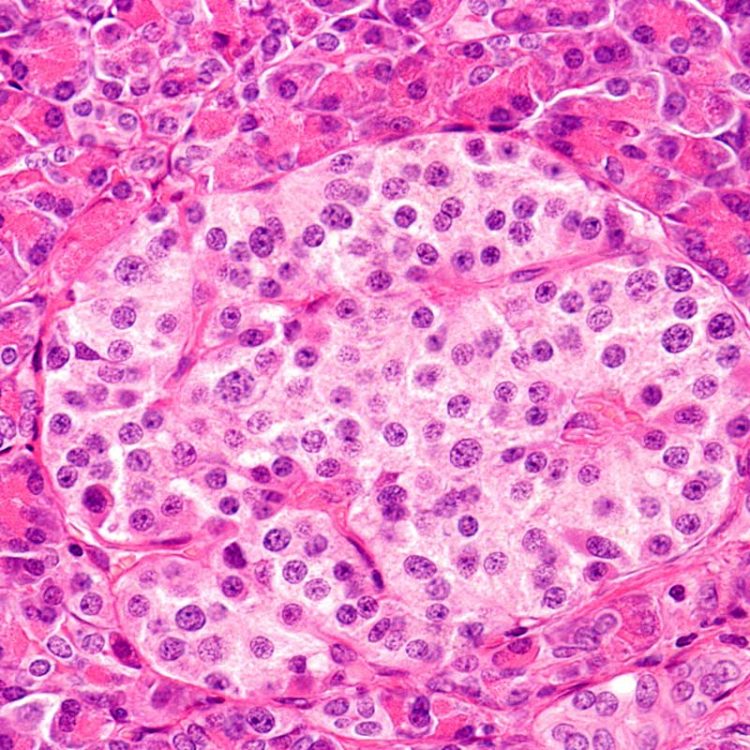

Autoimmunity arises when the immune system attacks and kills the body’s tissue. Type 1 Diabetes arises when the immune system destroys the in the insulin secreting cells in the pancreas. In Systemic Lupus Erythematosus (SLE) the immune system produces autoantibodies that bind to nucleic material, including double stranded DNA. The target in Multiple Sclerosis is the myelin sheath that protects nerve fibres in the central nervous system.